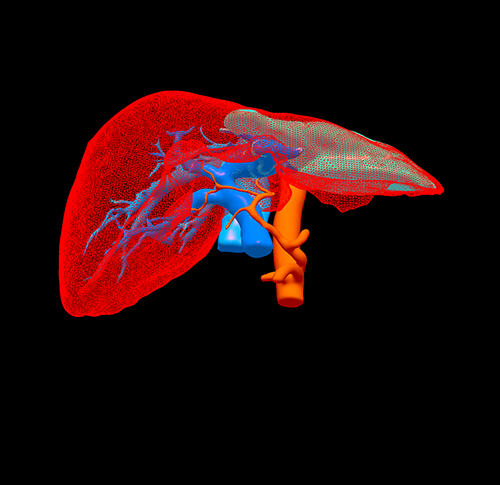

三维重建

左肝癌并门静脉左支癌栓---左半肝切除